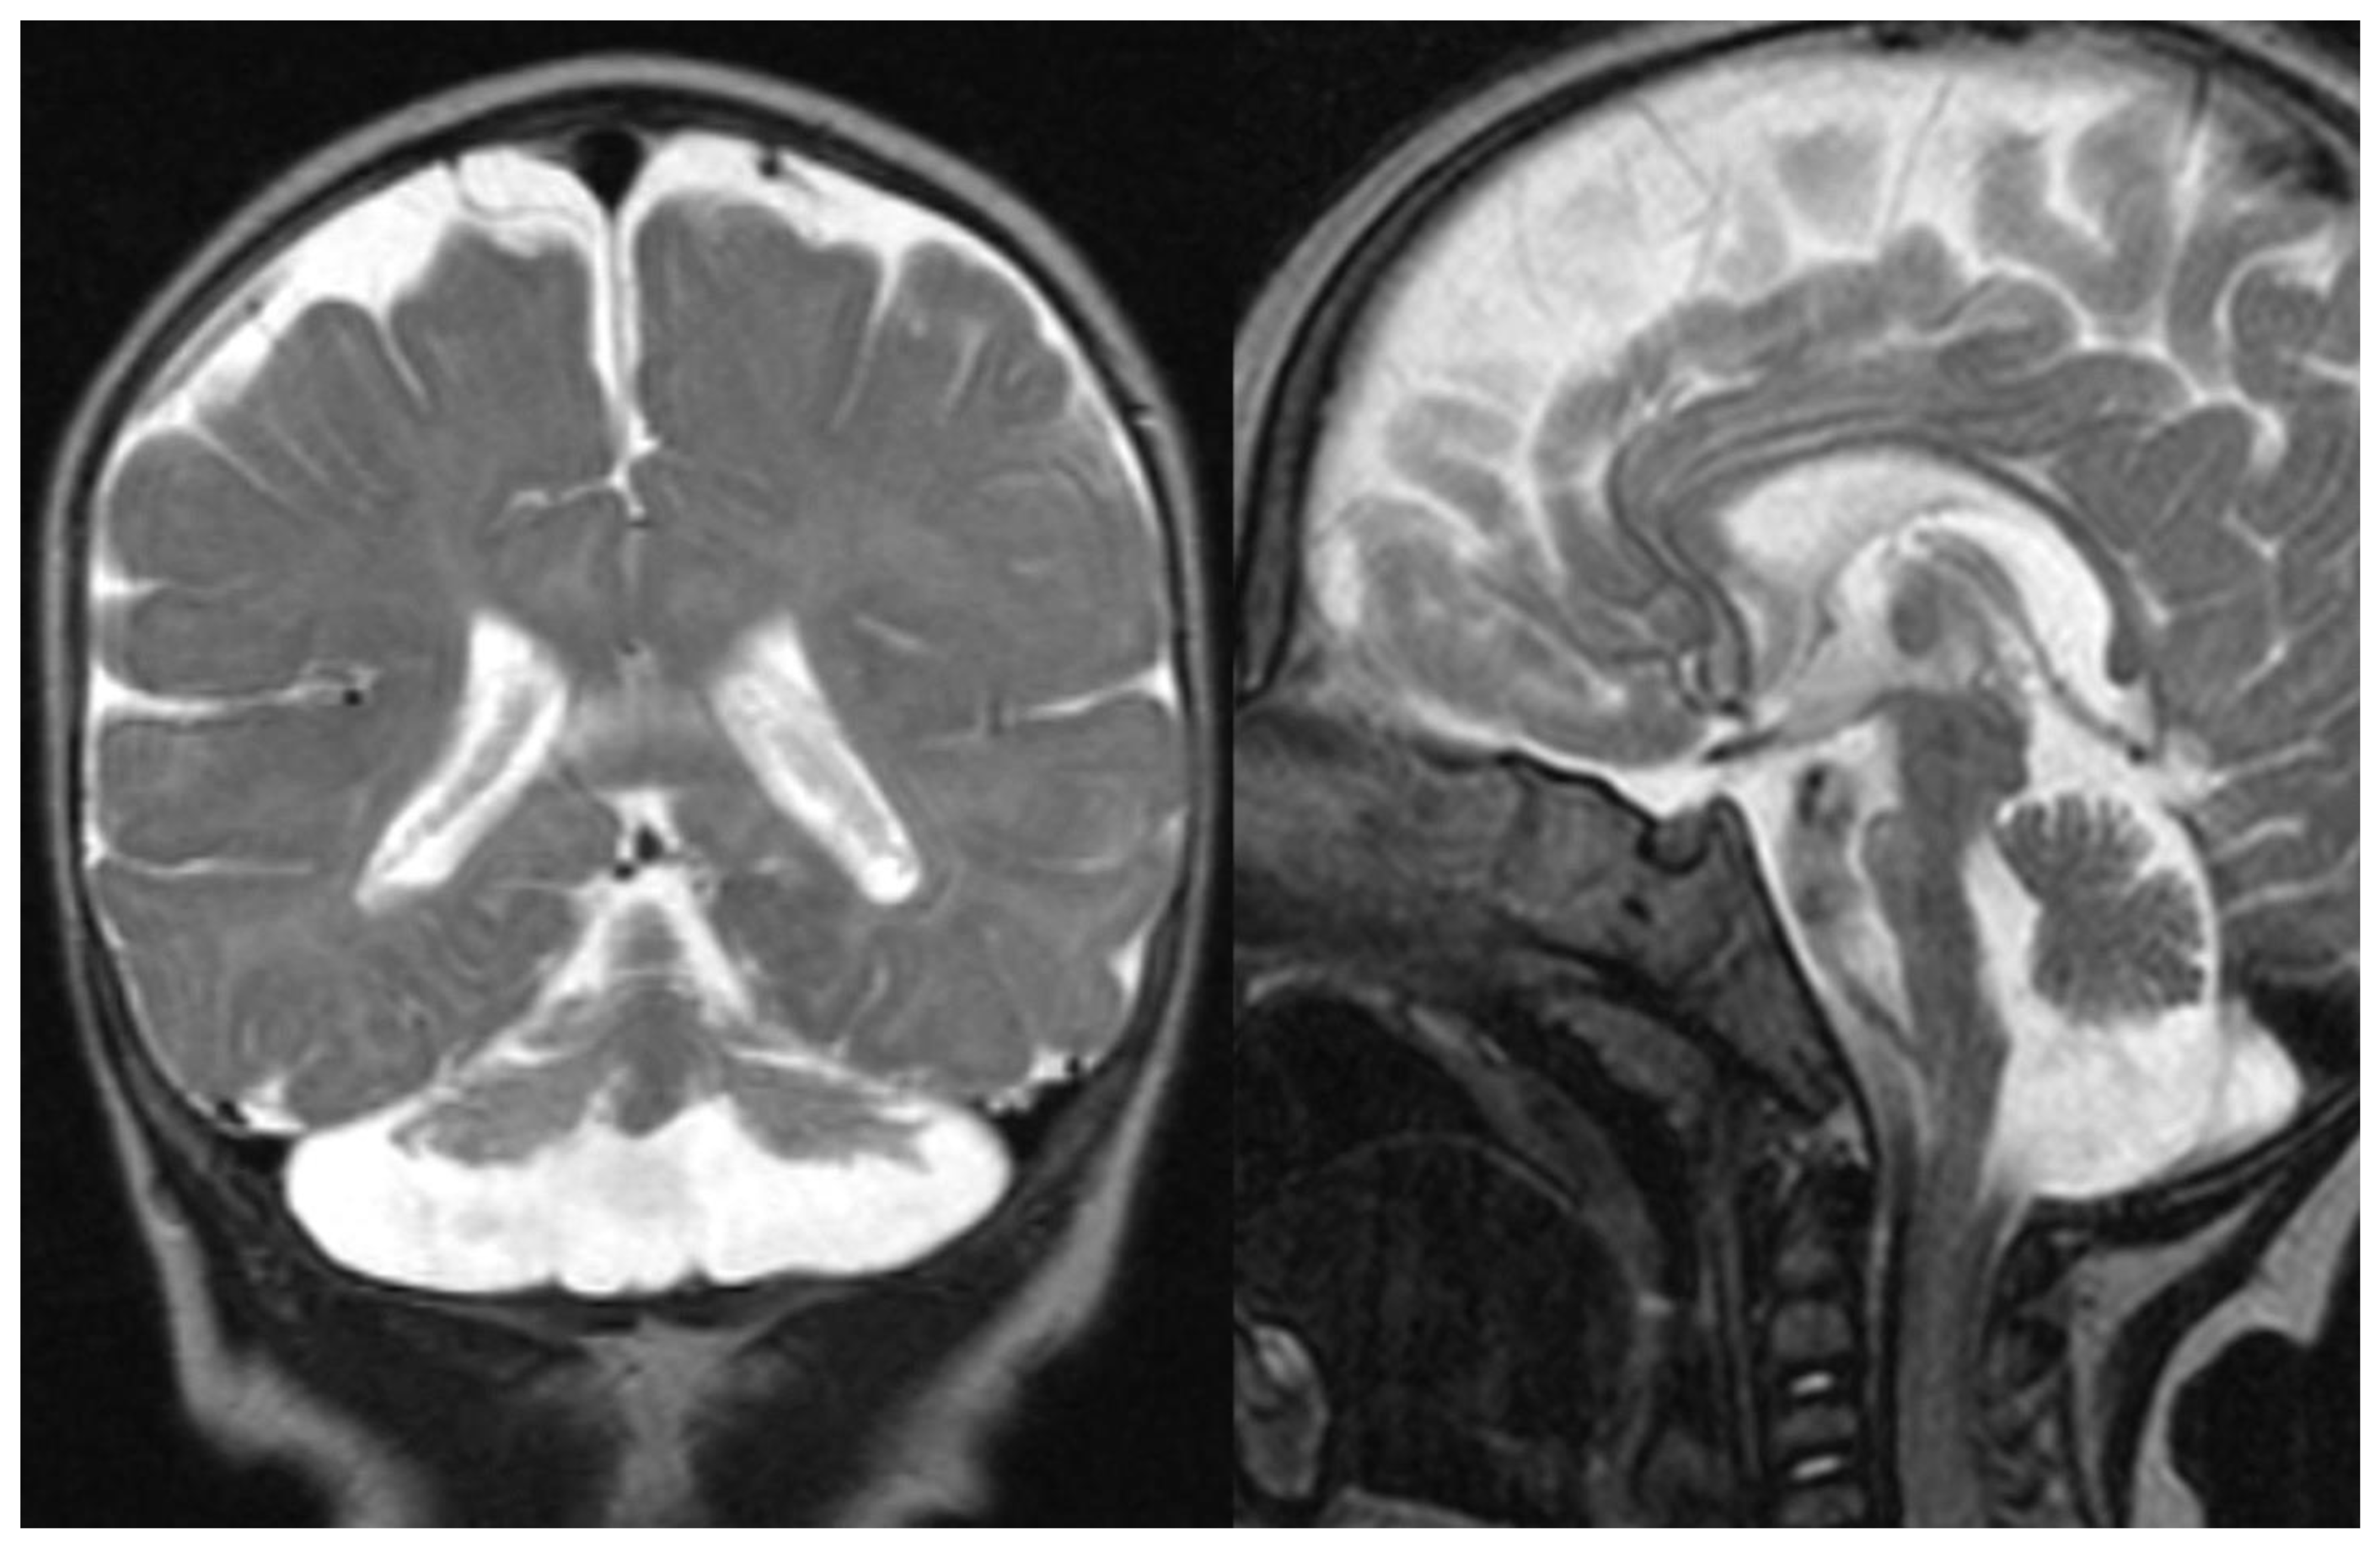

Overall, MRI in PCH patients shows a variable degree of cerebellar hypoplasia with involvement of pons and cerebrum. On coronal imaging, the particular shape of the cerebellum, named “dragonfly” or “butterfly” appearance, was described by Barth et al. [

5]. Additional inconstant findings are cerebellar cysts (PCH 1, 2, and 6), agenesis of the corpus callosum (PCH 9), simplified gyral pattern (PCH 6 and 10), and hypomyelination (PCH 1, 2, 6, and 9). In several PCH, pons could be relatively preserved, and in PCH10, the cerebellum is mostly normal 11. The presence of C-shaped inferior olive has been reported in PCH2, suggesting a prenatal onset 9 (

Figure 1).

A dragonfly-like pattern has been described in PCH 1, 2 (

Figure 1), 4, 6 (

Figure 1.

PCH 2. Brain MRI scan of a 1-year-old girl with TSEN 54 mutation. MR images demonstrate the characteristic “dragonfly-like” cerebellar pattern: severe hypoplasia of the cerebellar hemispheres with a relative sparing of the vermis. Note the flat ventral surface of the pons and thin corpus callosum.

Figure 1.

PCH 2. Brain MRI scan of a 1-year-old girl with TSEN 54 mutation. MR images demonstrate the characteristic “dragonfly-like” cerebellar pattern: severe hypoplasia of the cerebellar hemispheres with a relative sparing of the vermis. Note the flat ventral surface of the pons and thin corpus callosum.